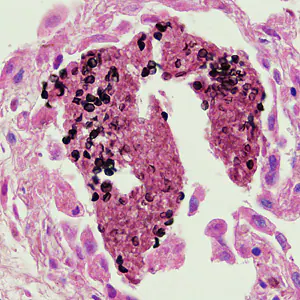

Pneumocystis jirovecii cysts.

The specific diagnosis is based on identification of P. jirovecii in bronchopulmonary secretions obtained as induced sputum or bronchoalveolar lavage (BAL) material. In situations where these two techniques cannot be used, transbronchial biopsy or open lung biopsy may prove necessary. Microscopic identification of P. jiroveci trophozoites and cysts is performed with stains that demonstrate either the nuclei of trophozoites and intracystic stages (such as Giemsa) or the cyst walls (such as the silver stains). In addition, immunofluorescence microscopy using monoclonal antibodies can identify the organisms with higher sensitivity than conventional microscopy.